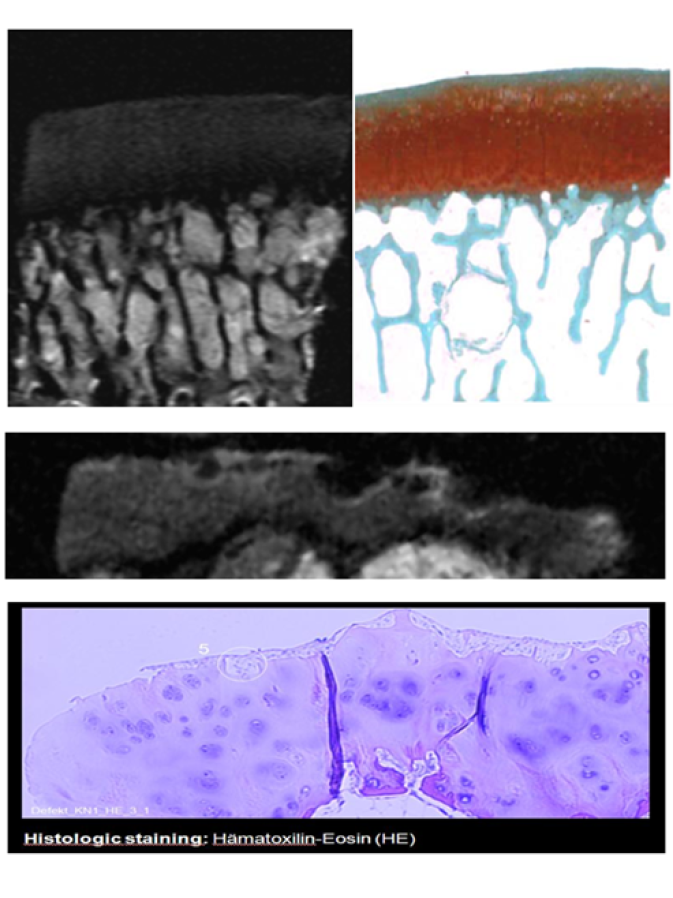

Es gibt eine Reihe von Geweben im menschlichen Körper (z.B. Sehnen, Meniskus, Zähne), die aufgrund des sehr schnellen Signalabfalls nicht hinsichtlich ihrer inneren Struktur sichtbar gemacht werden können. Methoden mit ultrakurzer Detektionszeit (UTE) in Verbindung mit der MR-Mikroskopie sind in der Lage, eine einzigartige morphologische Substruktur zu erkennen, z.B. die selbstähnliche Gewebeanatomie der Sehne (Abb. links). Auch die fraktale Dimension der selbstähnlichen Gewebetextur kann mit Hilfe von unterschiedlich Kontrast-gewichteten MR-mikroskopischen Daten und spezieller Datenverarbeitungssoftware ausgewertet werden [Berg et al. Proc. ISMRM 26, 2831 (2018)].

Obwohl die MR-Mikroskopie nicht die hohe Auflösung der Lichtmikroskopie erreichen kann, lassen sich Multi-Schicht-Bilder mit unterschiedlichem Kontrast mit einer Pixelgröße von etwa 30x30 µm2 erzeugen, was für die Erkennung von z.B. osteoarthritischen Veränderungen im Knorpel ausreichend ist. Der Hauptvorteil der MR-Mikroskopie mit unterschiedlich gewichteten Kontrastparametern liegt in der nicht-invasiven Bildgebung, ohne dass die Probe in dünne Scheiben geschnitten werden muss. Auch einige Färbevorgänge können vermieden werden, da die MR die Gewichtung des Signals mit unterschiedlichen Kontrastparametern ermöglicht (z.B. sd, T1, T2, T2*, Suszeptibilität, DWI, MT, ...) [Berg et. al. Proc. ECR EPOS #2914 (2011)], [Hager et. al., JMRI, 2022].